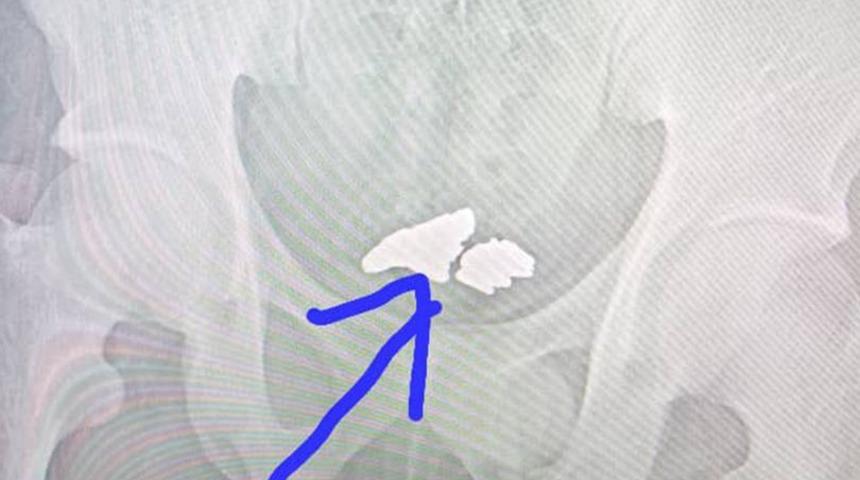

Adamın hastaneye götürülmesinden sonra çekilen ultrason görüntülerinde yuttuğu altınlar ortaya çıktı. Altınlar cerrahi operasyonla adamın midesinden çıkartıldı. İsmi açıklanmayan adam ise hırsızlık suçundan tutuklandı.